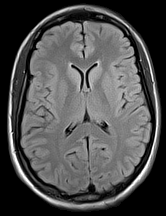

3.2.3 Example 2: Diffusion-weighted MRI (dMRI)

DMRI is an important MRI technique to study the neural architecture and connectivity of the brain. It is based on obtaining multiple 333-dimensional diffusion-weighted images to investigate the water diffusivity along various directions, being clinically important especially for the investigation of brain disorders, see e.g. (citep \@BBN(Shenton et al., 2012)). However, low signal-to-noise ratio and acquisition time limit the spatial resolution of dMRI and therefore its usage is currently mainly restricted to medium-to-large white matter structures, whereas very small cortical or sub-cortical regions cannot be traced accurately. To overcome this, several methods for increasing the spatial resolution of dMRI have been introcuded, see e.g. (citep \@BBN(Dyrby et al., 2014; Van Steenkiste et al., 2016; Grieve and Maller, 2017)).

Here, we study image data from an acquisition and reconstruction scheme for obtaining high spatial resolution dMRI images using multiple low resolution images, cf. (citep \@BBN(Ning et al., 2016)). The suggested method combines the concepts of compressed sensing and super-resolution to reconstruct high resolution diffusion data while allowing faster scan time. The data is visualized via the fractional anisotropy (FA) measures computed using diffusion tensor imaging (citep \@BBN(Basser, Mattiello, and LeBihan, 1994)).

The data from a human subject was acquired from a MGH connectome 3T scanner. Three thick-slice diffusion weighted imaging (DWI) volumes with voxel size 0.9×0.9×2.7mm30.90.92.7𝑚superscript𝑚30.9\times 0.9\times 2.7mm^{3}, TE/TR = 84/7600ms847600𝑚𝑠84/7600ms and 606060 gradient directions at b=2000s/mm2𝑏2000𝑠𝑚superscript𝑚2b=2000s/mm^{2}. A separate low-resolution isotropic DWI with a spatial resolution of 1.8×1.8×1.8mm31.81.81.8𝑚superscript𝑚31.8\times 1.8\times 1.8mm^{3} and with 606060 gradient directions at b=2000s/mm2𝑏2000𝑠𝑚superscript𝑚2b=2000s/mm^{2}.

The super resolution image in 6(a), serving as a reference here, was obtained using the super-resolution reconstruction technique that combines multiple thick-slice DWI with all 60 diffusion directions into a high-resolution image, cf. (citep \@BBN(Ramos-Llordén et al., 2020)). This technique yields a high quality image with good detail preservation, but takes much longer scan time than the standard upsampling method in 6(c), where the FA map of the low-resolution data was up-sampled using 3DSlicer (citep \@BBN(Fedorov et al., 2012)) to the higher resolution.

The image in 6(b), cf. (citep \@BBN(Ning et al., 2016)), was obtained using a combined super-resolution reconstruction, compressive sensing, and spatial regularization techniques with thick-slice images, where each thick-slice DWI has a different set of 202020 diffusion gradient directions, saving indispensable scan time. The advanced method yields a much higher visual quality image than 6(c), preserving more anatomical details.

Refer to caption

(a) Reference

(b) (17.62, 0.57, 0.19)

(c) (18.23, 0.58, 0.26)

Figure 6: Visualized FA images obtained from diffusion MRI with super-resolution reconstructions. The up-sampled image (c) is wrongly judged to have better quality than the high-resolution reconstruction (b) by PSNR and SSIM, LPIPS judges this task correctly.

FR-IQA mismatch

We can see in Figure 6 that PSNR and SSIM misjudge the visual quality of the high-resolution reconstruction in (b) in comparison to the up-sampled image in (c). Clearly, that image has worse visual quality than the one in (b). It is per default more blurry and does not provide sufficient anatomical details. LPIPS yields more sufficient results in this example, and correctly attributes (c) a higher quality error.

In this example it has to be noted that the computed IQA numbers are generally quite low, because the resulting FA images do not necessarily have to have the same range or distribution as the reference image. Therefore, in order to compare the reconstruction quality directly, this task generally benefits from NR-IQA evaluation.